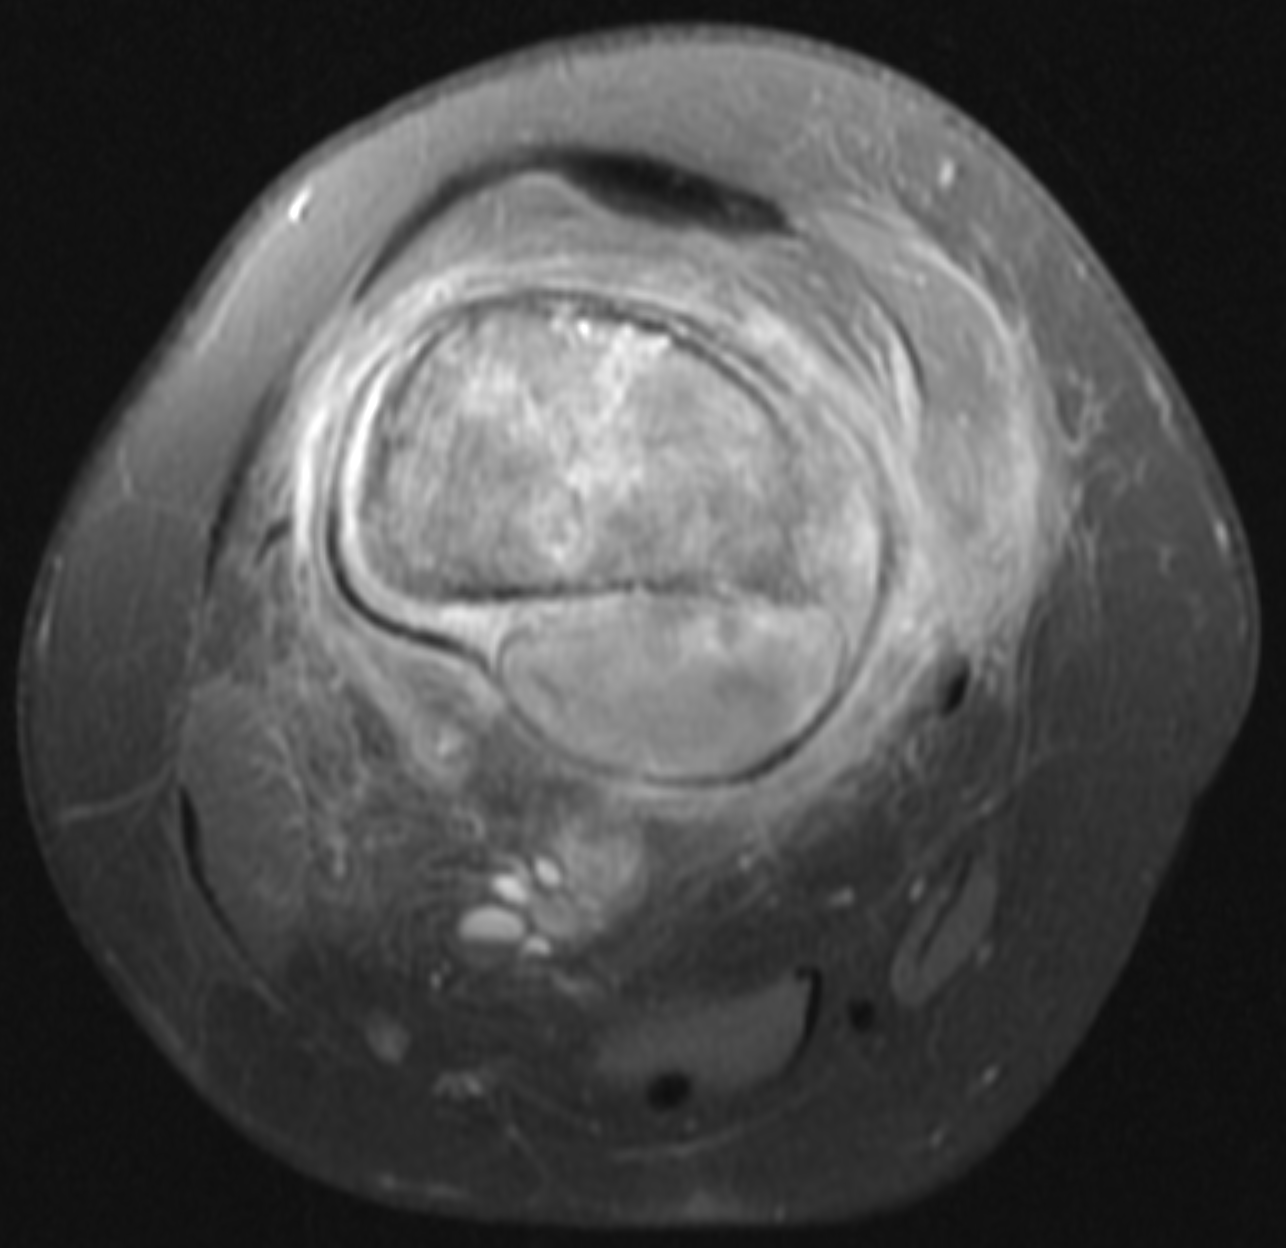

IGTFusion used to guide and confirm accurate biopsy needle placement in soft tissue mass adjacent to femoral bone tumor that was not visible on CT during the procedure, but was visible on the pre-treatment MRI.

- Registered a pre-procedure MRI with procedural CT

- Fusion adjusts for rotation of femur between images due to leg positioning

- Saved procedure time by identifying the occult soft tissue mass for biopsy